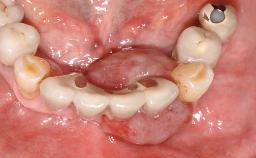

Oral implants are highly successful and offer long-term benefits, especially in the rehabilitation of edentulous patients or patients with oral defects following ablative tumor surgery (Albrektsson and coworkers 1986), and also after radiation therapy (Schiegnitz and coworkers 2014). With the number of implants placed globally going into the millions, implant dentists have observed some rare adverse events. Although carcinogenesis around implants is an exceedingly rare phenomenon, we recently reported about 15 patients treated for carcinomas adjacent to implants at our clinical department over a period of fifteen years (Moergel and coworkers 2014). The following case represents a patient of this cohort; it discusses possible risk factors and makes suggestions for a recall schedule. A 70-year-old woman was referred to our outpatient department for evaluation of a rapidly growing macroscopic alteration of the mucosa in the left mandible.

Jaw Mandible

Area Posterior

# of Teeth 7

# of Implants 4